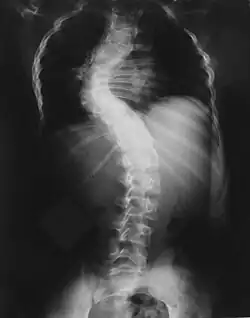

Im Altersbereich bis zu 12 Jahren kann es zu Verformungen der Wirbelkörper kommen, die zu einer schweren Skoliose führen können. Eine frühzeitige und regelmäßige Vorstellung bei einem mit NF1 vertrauten Spezialisten ist daher ratsam.

Skelettveränderungen treten bei einem Drittel der Patienten auf und bringen die Neurofibromatose-Patienten zum Orthopäden.

Sehr häufig finden sich Wirbelsäulenveränderungen von einfacher über kurzbogiger und knickförmiger Skoliose bis extrem ausgeprägten Kyphoskoliosen aufgrund von Fehlentwicklung der Wirbelkörper.[16]

Als klinisches Spektrum bezeichnet man alle Symptome, die ein Patient mit einer bestimmten Erkrankung bekommen kann und deren Entstehung in einen kausalen Zusammenhang mit der Erkrankung gebracht wird, also nicht bloß zufällig ist. Bei den meisten Autoren gelten folgende Symptome als obligatorisches klinisches Spektrum der Neurofibromatose Typ 1: Café-au-lait-Flecken und kutane Neurofibrome zählen dazu. Der Nachweis von Lisch-Noduli gelingt je nach Studie bei 90 bis 100 Prozent der Patienten. Bei ca. 80 Prozent der Patienten findet sich eine sommersprossenartige Pigmentierung der Achselhöhle. Bei 20 Prozent der Patienten findet man große plexiforme Tumoren. Alle anderen Tumoren (spinale und periphere Neurofibrome, Schwannome der peripheren Nerven et cetera) finden sich bei weniger als fünf Prozent der Patienten. Etwa ein Drittel der Patienten hat darüber hinaus unspezifische Symptome wie Schulprobleme (30 Prozent), Minderwuchs (15 Prozent), Macrozephalie (25 Prozent) und Skoliosen (30 Prozent). Pseudoarthrosen und Epilepsien treten bei weniger als fünf Prozent der Patienten auf. Ein Teil der Patienten entwickelt ein Phäochromozytom.